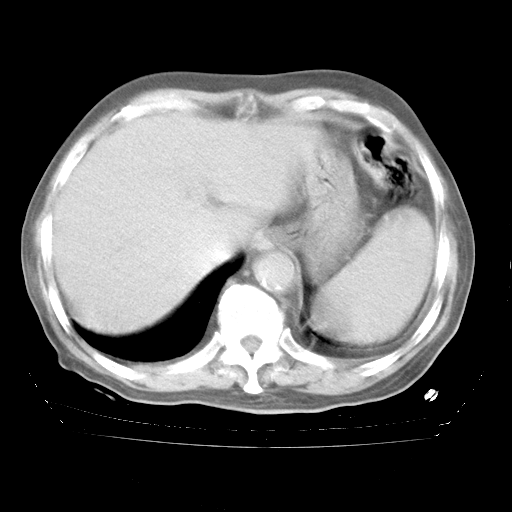

4月28日肺部CT——再次出现类似去年5月9日——透光度降低,“间质性”改变。

4月28日肺部CT